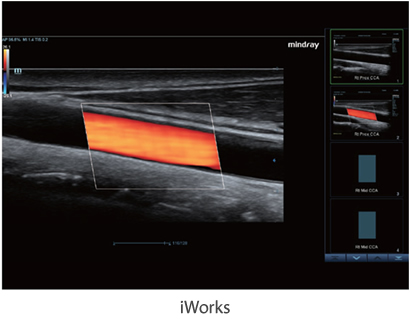

X-Insight to rozwi?zanie umo?liwiaj?ce wnikliw? analiz?, zapewniaj?c bardziej szczeg├│?owy obraz.

Opieraj?c si? na analizie potrzeb klienta, DC-60 Exp X-Insight zosta? zaprojektowany tak, aby znacznie usprawni? diagnostyk?, kt├│ra jest wspomagana przez technologi? eXpress Clarity, eXceptional Intelligence i eXceeding Experience.

Obrazy kliniczne